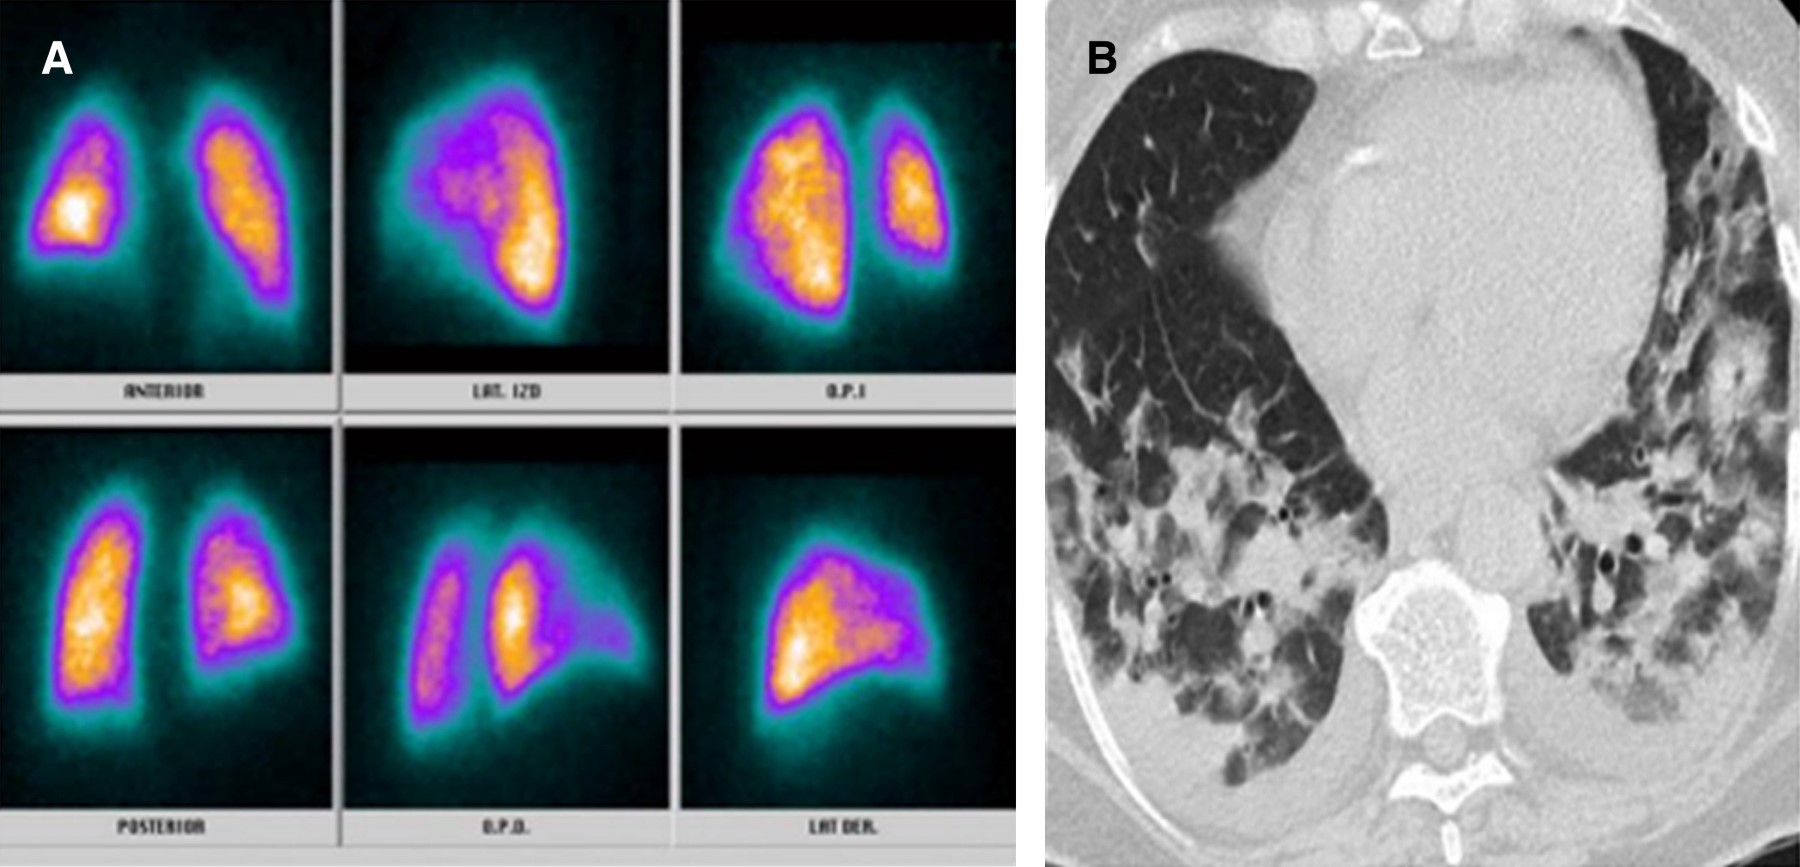

La infección por nuevo coronavirus es una entidad clínica altamente letal que trae consigo serias disfunciones celulares en primera línea de defensa, lo cual genera potentes mecanismos de hipercoagulabilidad mediados por reclutamiento de células inflamatorias.1 Uno de ellos direccionado por la disfunción del polimorfonuclear a partir del receptor 2 de enzima convertidora de angiotensina generado por la interacción de la fenilalanina ubicada en la porción 486 de la proteína de espiga del coronavirus, constituyéndose como el efecto más quimiotáctico existente, incluso superior al de la interleucina 8 (IL-8).2 A partir de esta situación, el reclutamiento del neutrófilo trae consigo la formación de una fina red inflamatoria inductora de integrinas denominadas NET (Neutrophil Extracellular Traps), produciendo activación de la vía intrínseca de la coagulación a partir del factor XII de Hageman. Adicionalmente, la muerte programada de dichas células, mediante la inducción de apoptosis, ocasiona liberación de histonas y restos de ADN, lo que precipita la formación de trombina.3,4 Por otro lado, la infección por nuevo coronavirus altera la respuesta del huésped al inóculo mediante modificación de los micro-ARN linfocitarios, lo que ocasiona disfunción del fagosoma natural en estadios de inmunocompetencia exacerbada o inmunosupresión manifiesta que a la postre desencadena estrés oxidativo, liberando grupos de proteínas de elevada movilidad (High Mobility Protein Box 1 [HMGB1]) y generando inflamación, coagulación y apoptosis.5 Pero, sin duda alguna, la linfopenia inducida por el coronavirus tipo 2 se constituye como el determinante más letal de trombosis mediante activación de la vía extrínseca e intrínseca de la coagulación, de la mano de un influjo descomunal de trombina. Se han identificado tres mecanismos de muerte celular programada en el linfocito de pacientes con la enfermedad por coronavirus del 2019 (COVID-19); uno de ellos es por activación del factor de transcripción nuclear y factor nuclear kappa beta, otra es por la activación del mitógeno p37 de la proteincinasa y la más deletérea mediante autofagocitosis determinante de un potente estado protrombótico.6 Con base en el conocimiento de los escenarios disfuncionales hematológicos durante la infección por nuevo coronavirus, se hace perentoria la predicción de enfermedad pulmonar tromboembólica, existiendo la duda razonable entre la prevención y la terapia antitrombótica, motivo por el cual la presencia de marcadores de actividad de fibrinolítica debe ser validada en tiempo presente y real. Teniendo en cuenta la mejor sensibilidad y especificidad disponible, las diferentes técnicas de enzimas líticas de inmunoensayo, hemaglutinación y látex deben someterse a consideración durante la estratificación diagnóstica.7,8 Una vez discriminados los pacientes con SARS-CoV-2 con pretest clínico medio para enfermedad pulmonar tromboembólica con reporte de dímero D por técnica de látex positivo y cuyos resultados de angio-TAC descartaron tromboembolia pulmonar (TEP); se les documentó, desde el punto de vista imagenológico, los defectos segmentarios de distribución vascular con morfología triangular de base externa y vértice interno por medicina nuclear, los cuales se correlacionaron muy de cerca con hallazgos en escanografías simples de tórax con atelectasias, efusión pleural y condensaciones, así mismo la presencia de alta probabilidad para TEP se validó por criterios de PISAPED (Figura 1, 2, 3, 4, 5, 6 y 7).9

Figura 2